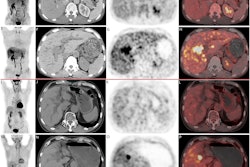

A: F-18 FAPI-04 PET/CT and CT images of a patient with locally advanced esophageal squamous cell carcinoma (LA-ESCC) with an outcome classified as partial response. B: F-18 FAPI-04 PET/CT and CT images of an LA-ESCC patient with an outcome classified as stable disease. Images courtesy of the Journal of Nuclear Medicine."The ability to identify patients with a poor prognosis in advance via imaging will help to realize individualized treatment of tumors," wrote corresponding author Dr. Shuanghu Yuan, PhD.

This trial was conducted between June 2021 to March 2022 and included 18 patients with LA-ESCC who underwent F-18 FAPI-04 PET/CT imaging before chemoradiotherapy. Four weeks after treatment, patients were split into groups to determine who showed a complete response, partial response, stable disease, or no response.

The researchers evaluated standard uptake (SUV) values based on tumor uptake of the F-18 FAPI-04 radiotracer, as well as target-to-background ratios (TBR) between the groups. At baseline, quantitative measures of patient response were significantly higher in those patients who did not respond to treatment compared to those who did -- specifically TBRblood (12.53 vs. 10.29), TBRmuscle (12.24 vs. 9.81), and SUVmean (14.30 vs. 4.25), Yuan's group reported.